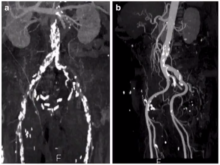

Heyman Luckraz of the American Hospital Dubai, UAE, presents an overview of different access routes for transcatheter aortic valve replacement. He discusses the benefits and challenges of the different routes, including transfemoral, transapical, and transcaval.